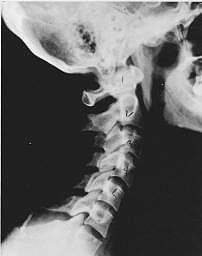

Phase One - Subluxation Degeneration

Subluxation Degeneration - Phase One Phase One Subluxation Degeneration is seen in subluxations that have been present for up to twenty years. This phase is characterized with a loss or change in the normal curve in the spine. On this example you can see that the normal forward (lordotic) curve is lost. This spine even has developed a reverse curve in the neck. The disc spaces have also begun to exhibit a slight change in shape. One good point is that the bodies of each of the vertebrae (the square part in front) still exhibits clean clear borders. Segmental motion may be abnormal but overall motion is probably not affected. Chiropractic reconstructive care for a phase one can take from 6 to 18 months. More than 80% of people with Phase One Subluxation Degeneration have no pain. Therefore, if left uncorrected, phase one continues to progress with time until it eventually reaches the next phase.